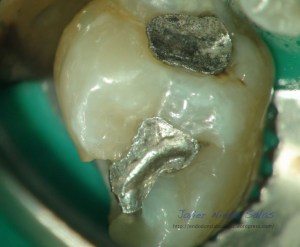

Una de sus muchas ventajas, las cuales no voy a entrar a describir ahora, es la facilidad de poder conservar en la fase de apertura el tejido remanente de la corona, no es necesario realizar una apertura deficiente para que sea conservadora, gracias a la magnificación y la luz coaxial, podemos tallar la cámara pulpar lo justo y necesario para localizar y preparar los conductos sin necesidad de hacer una gran apertura, necesaria para poder trabajar sin esta opción.

El caso de hoy, se trata de ver esta ventaja que podemos ofrecer en algunos casos a nuestros pacientes, no en todos, por que la disposición de los conductos y la caries , nos van a condicionar.No quisiera destacar tanto el tratamiento en sí, y darle más importancia a la apertura, fase muy importante, capaz de hacer, en muchas ocasiones que una endodoncia se complique o sea más sencilla.